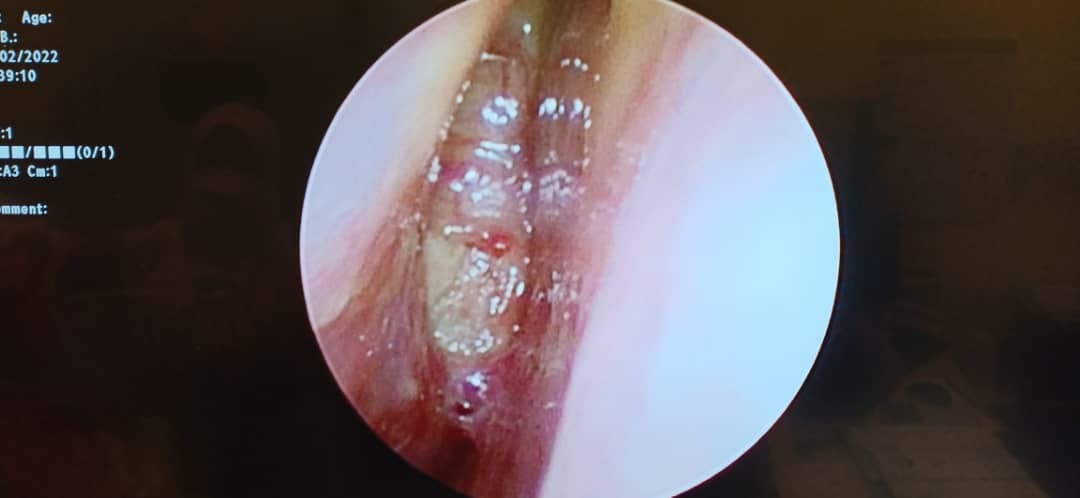

Schwannomas, also known as neurilemmomas, are benign nerve sheath tumors originating from Schwann cells of the peripheral nervous system. Sinonasal schwannomas are rare, comprising approximately 4% of all schwannomas. These tumors are typically slow growing, often leading to delayed clinical presentation. Despite their benign nature, their indolent progression can result in significant morbidity due to mass effect on adjacent vital structures. We report a case of a large, late-diagnosed right sinonasal ancient schwannoma causing extensive compression of surrounding tissues, including the right frontal and temporal lobes, ultimately resulting in vision loss due to compressive optic neuropathy. Ocular symptoms may be the initial manifestation of sinonasal tumors and should raise concern for potentially aggressive lesions. Prompt recognition and early referral are critical to minimize complications and improve patient outcomes.